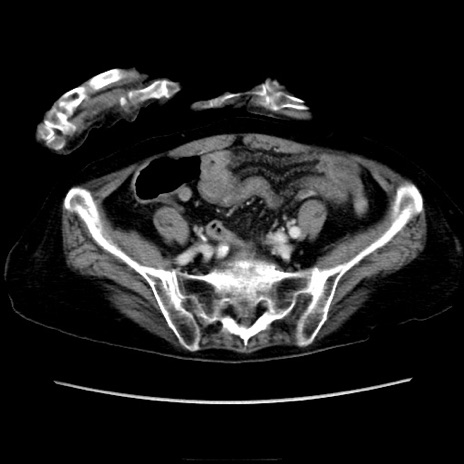

症例40(横断像)

横断像